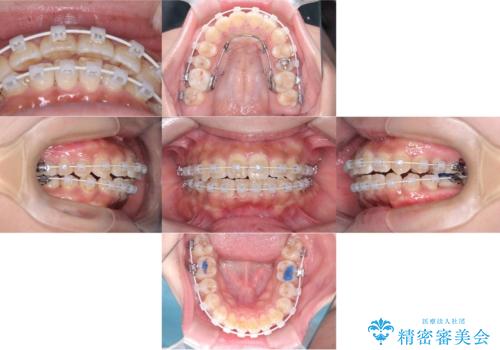

ワイヤー矯正(審美装置)非抜歯 治療期間:1年8か月

途中、大臼歯の遠心移動のためリンガルアーチを使用しています。